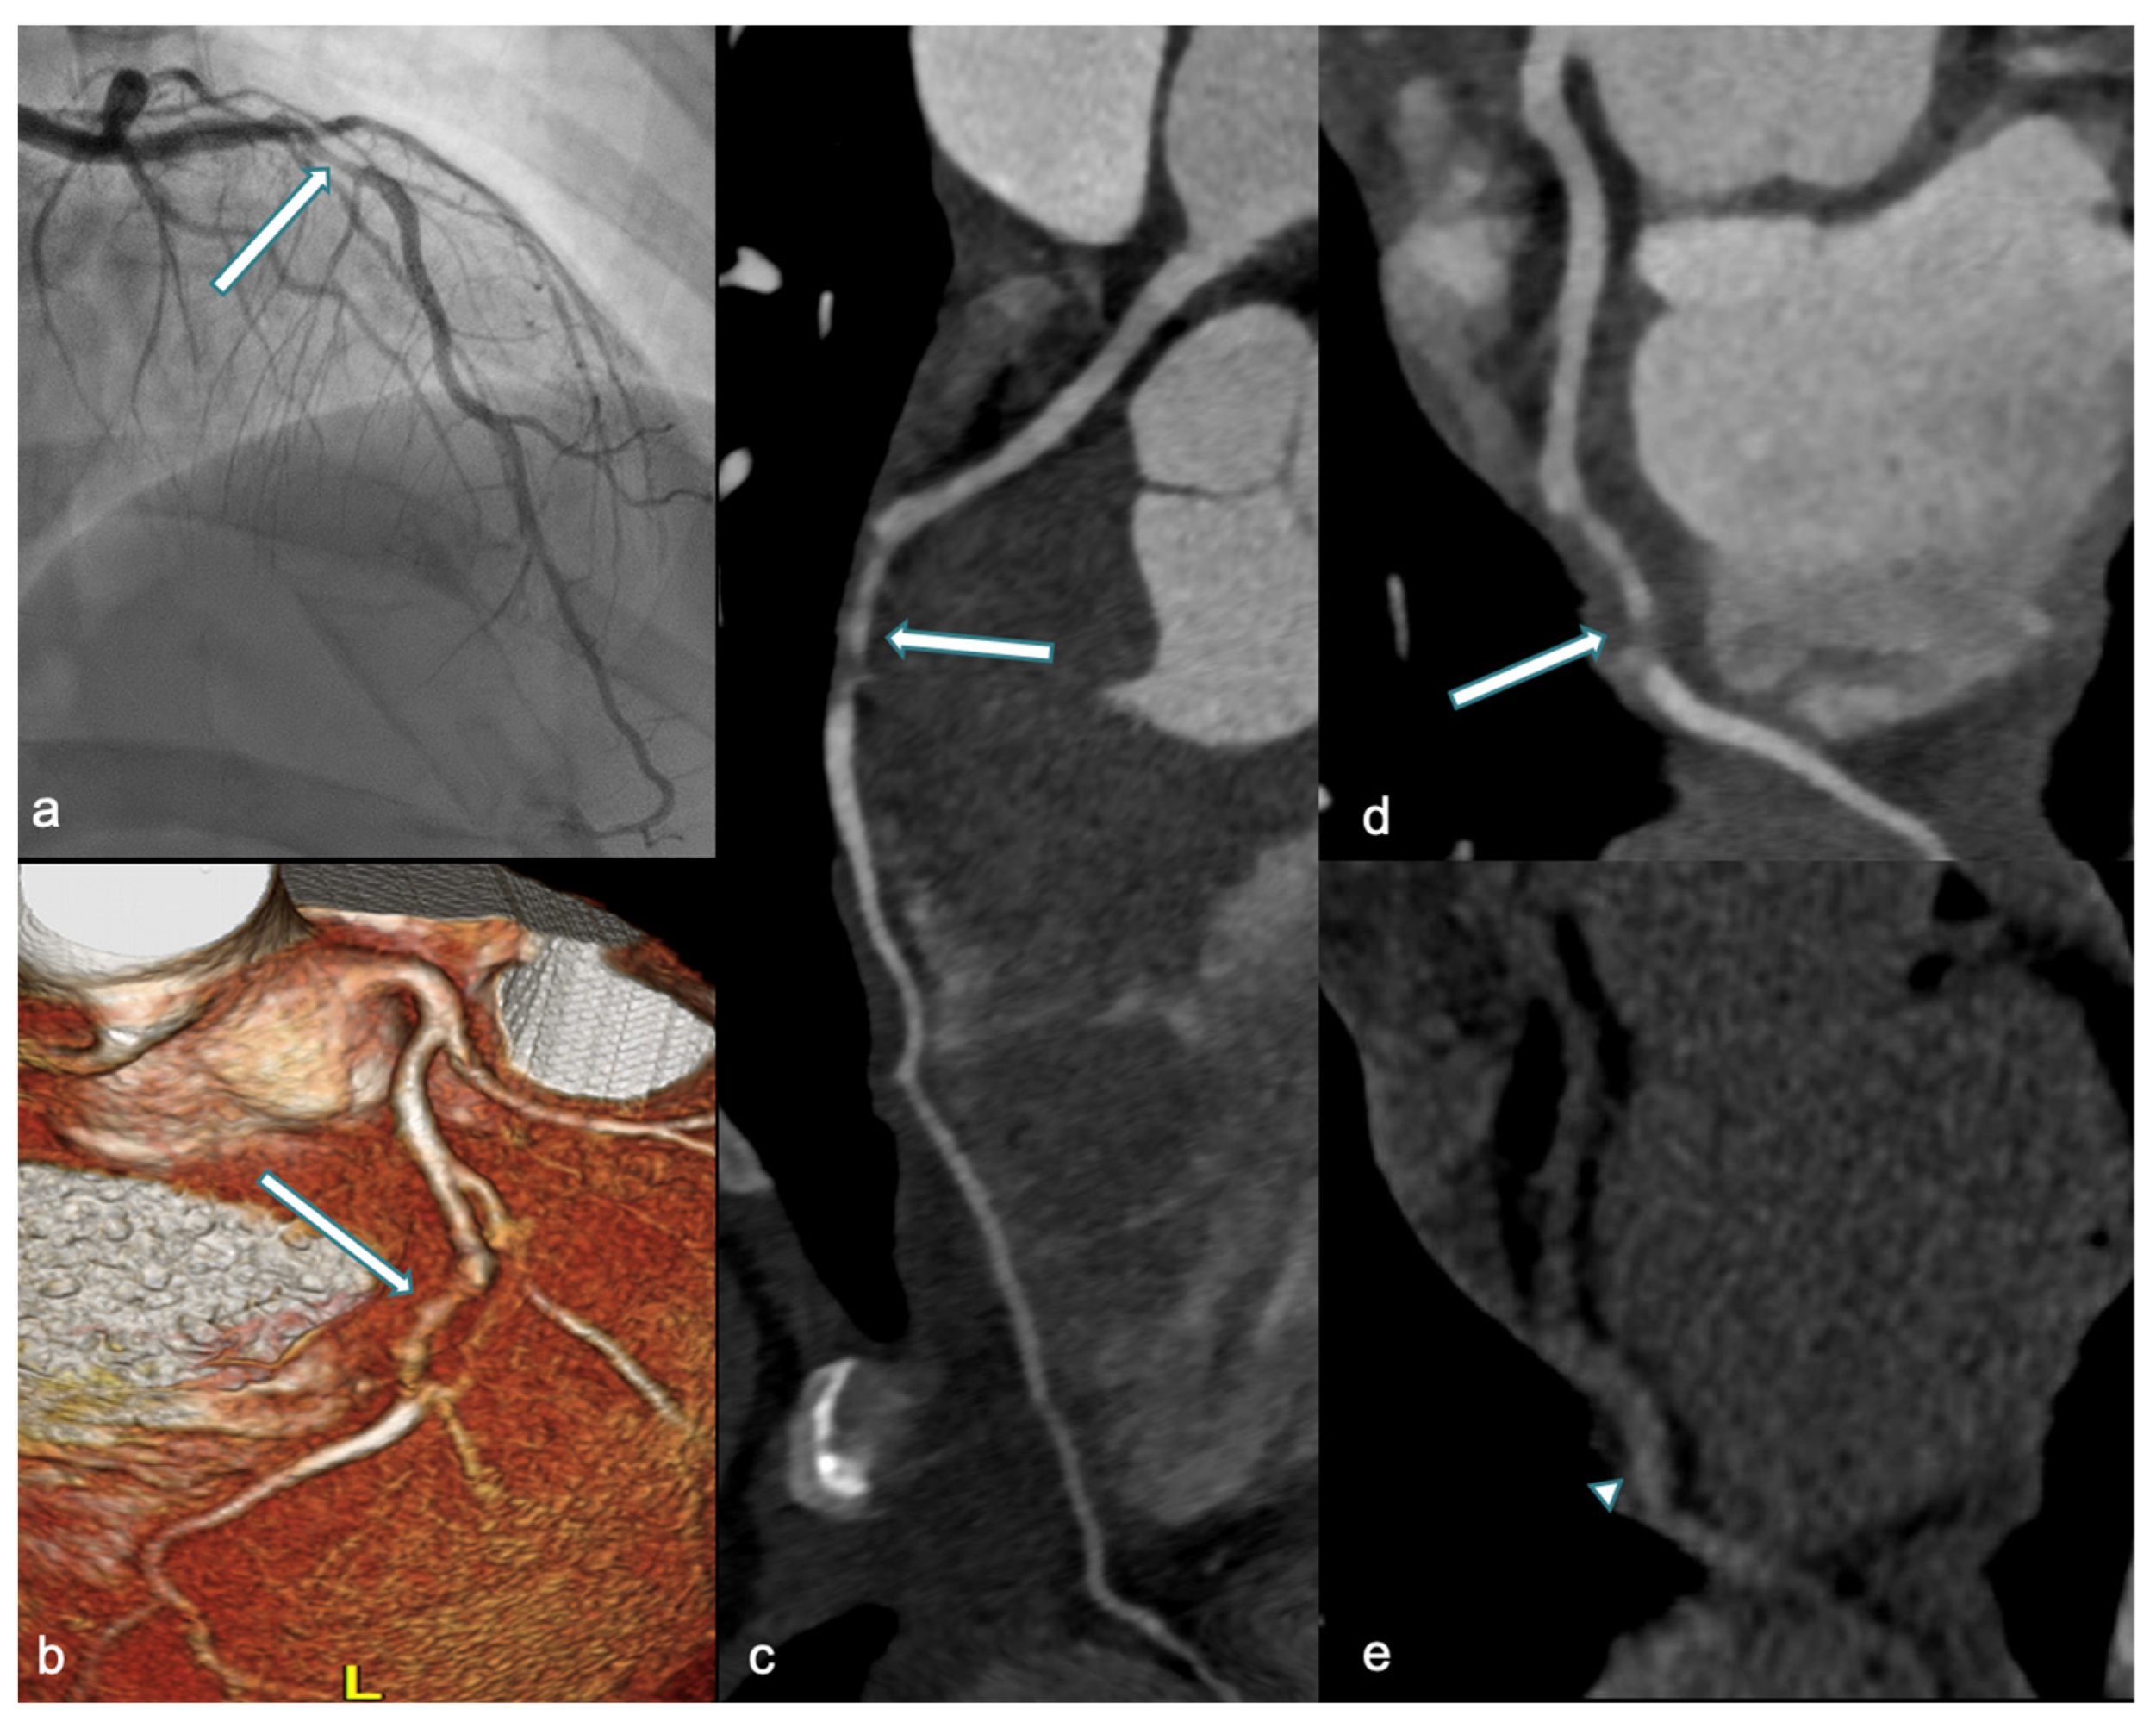

5.1. CCTA: Roles and Findings

- Pergola, V.; Continisio, S.; Mantovani, F.; Motta, R.; Mattesi, G.; Marrazzo, G.; Dellino, C.M.; Montonati, C.; De Conti, G.; Galzerano, D.; et al. Spontaneous coronary artery dissection: The emerging role of coronary computed tomography. Eur. Heart J. Cardiovasc. Imaging. 2023, 24, 839–850. [Google Scholar] [CrossRef]

- Tweet, M.S.; Akhtar, N.J.; Hayes, S.N.; Best, P.J.; Gulati, R.; Araoz, P.A. Spontaneous coronary artery dissection: Acute findings on coronary computed tomography angiography. Eur. Heart J. Acute Cardiovasc. Care 2019, 8, 467–475. [Google Scholar] [CrossRef]

- Aslam, A.; Stojanovska, J.; Khokhar, U.S.; Weinberg, R.L.; Ganesh, S.K.; Labounty, T.; Sutton, N.R.; Patel, S. Spontaneous Coronary Artery Dissection: An Underdiagnosed Clinical Entity-A Primer for Cardiac Imagers. Radiographics 2021, 41, 1897–1915. [Google Scholar] [CrossRef] [PubMed]